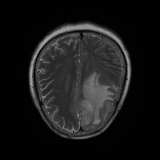

We obtain a subject-wise mean Dice score of 32.94% without any post-processing. By using a simple post-processing with erosion and dilation with filters, this number improves to 48.20% mean Dice score. In comparison, a similar study conducted by [3] consisting of a multitude of algorithms including AnoVAEGAN [4] and f-AnoGANS, obtained a best mean score of 27.8% Dice after post-processing by f-AnoGANS. Before post-processing the best method was Constrained AutoEncoder [8] with a score of 9.7% Dice. An exhaustive list is presented in Table 1. Figure 4 shows sample images of our results.

We obtain a subject-wise mean Dice score of 63.67% for the brain tumor segmentation. Utilizing a simple post-processing scheme of erosion and dilation with filter, we improve our mean Dice score to 68.01%. Figure 4 shows samples generated by our ASC-Net and Table 2 shows our before and after post-processing results. We attempted to apply f-AnoGANs [34] by following their online instructions and failed to generate good reconstructions as shown in Figure 5. The failure of AnoGANs in the reconstruction brings to light the issue with the regeneration based methods and the complexity and stability of GAN-based image reconstruction.

We obtain a slice-wise mean Dice score of 32.24% for this liver lesion segmentation, which improves to 50.23% by using a simple post processing scheme of erosion and dilation with filter. Sampled results are shown in Fig. 4. Compared with [42], which obtains a mean Dice score of 40.78% and a standard deviation of 0.43%, we improve the mean Dice score by almost 10%, but has a much larger standard deviation. Unlike [42], where the network is pre-trained on a artificial tumor dataset, and hence the pipeline customized for tumor segmentation, our method do not need such information beforehand. We notice that our standard deviation for BraTS dataset is similar to [27]. This is because novelty/anomaly detection algorithms without a pre-defined task would suffer from the co-morbidities issues discussed in Section 5.